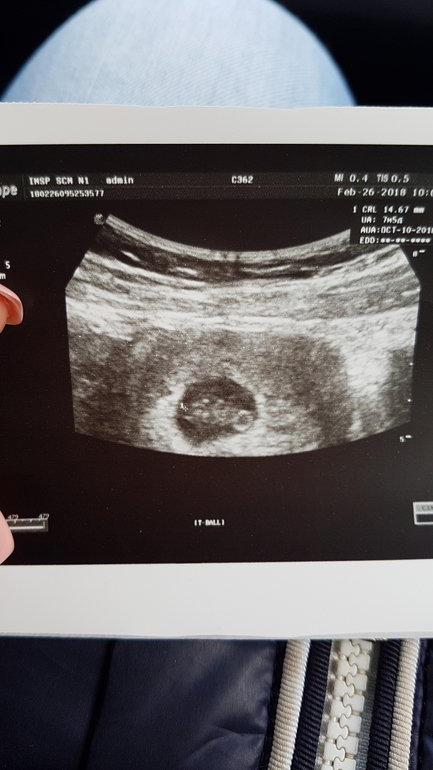

Первое узи)))

Вопросы про УЗИ, обследования и анализы: что, где, как, когда?Вот мы и сделали узи.слава богу все хорошо сердечко бьется,счастье ростом в 25мм)))по узи 7-8 недель.узист говорит девочка бцдет (с мальчиком угадал)посмотрим на этот раз угадал ли.в общем выдохнула я с облегчением что все у нас хорошо дай бог чтобы и дальше так было.

Вишенка наша😍😍😍😍